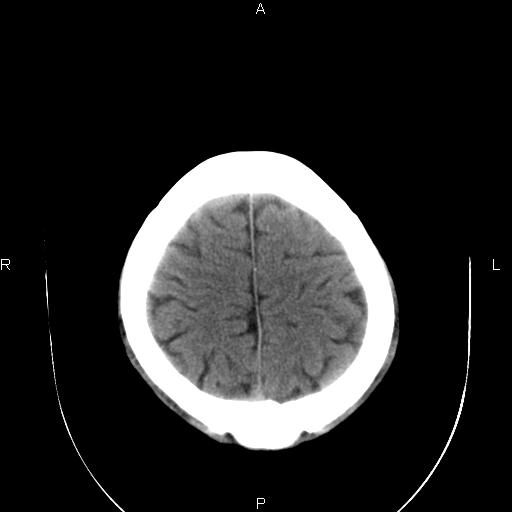

男性,40岁,反复头痛,视物旋转一月余,无呕吐,pe未见明确异常。

我的问题是上矢状窦高密度怎么解释?请各位专家不吝指教,谢谢!

可结合增强或mrv检查除外上矢状窦血栓。